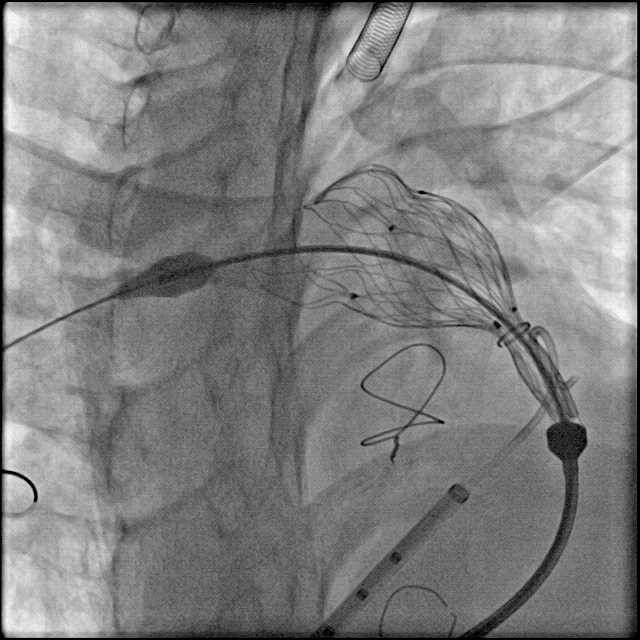

术中肺动脉造影:

重度肺动脉瓣关闭不全,大量返流。

肺动脉造影测量肺动脉内径等参数:

术中球囊压迫试验:

送入超硬导丝建立轨道,送入顺应性球囊,球囊膨胀的同时行左冠状动脉造影,可见冠脉血流通畅,球囊未压迫冠状动脉。

使用顺应性球囊测量肺动脉内径等参数:

送入输送系统:

根据术前CT、术中造影及球囊测量结果,选择P34-25型号的VenusP-Valve瓣膜,使用圈套器辅助,沿超硬导丝送输送器至肺动脉分叉处。

缓慢释放瓣膜,造影确认人工瓣膜起始位置准确:

继续释放瓣膜,反复造影确认人工瓣膜位置准确:

人工瓣膜释放完成,缓慢退出输送器:

造影确认无明显瓣周漏: